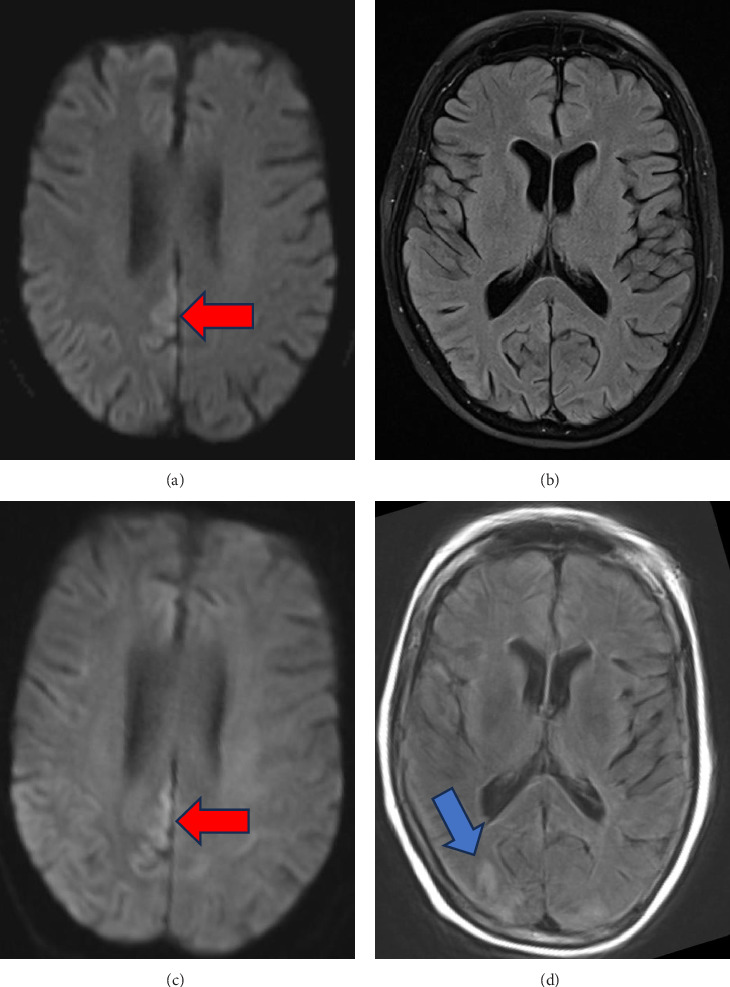

Presenting symptoms of sporadic Creutzfeldt-Jakob disease (sCJD) are variable, and as imaging and EEG may be normal in the early to middle stages of the disease process, serial testing is vital when there is clinical suspicion for sCJD. We present a case of probable Heidenhain variant of sCJD (HvCJD) with notable rapid progression. A 72-year-old woman presented with neurological decline following new-onset visual changes. Over the course of 3 weeks, she developed ataxia followed by paranoia, memory impairment, and visual hallucinations. An extensive workup from 1 week prior at an outside hospital was unrevealing and included two magnetic resonance imaging (MRI) studies read as normal and an EEG without periodic sharp wave complexes. Repeat of imaging at our hospital showed cortical restricted diffusion in the right occipital lobe. In combination with new periodic sharp wave complexes visualized on prolonged EEG, concern was raised for sCJD. Palliative care was consulted early in the hospitalization, and the patient was transitioned to comfort care and discharged 3 days after admission. She declined quickly and passed away at home within a week, one day before her send out CSF sample resulted with a positive real-time quaking-induced conversion (RT-QuiC) and markedly elevated T-tau protein and 14-3-3 gamma. As there is no treatment for this fatal disease, palliative engagement and discussion of goals of care in cases of CJD is critical in providing compassionate care for the patient and their family. High clinical suspicion warrants discussion of comfort care measures even prior to confirmation with RT-QuiC.